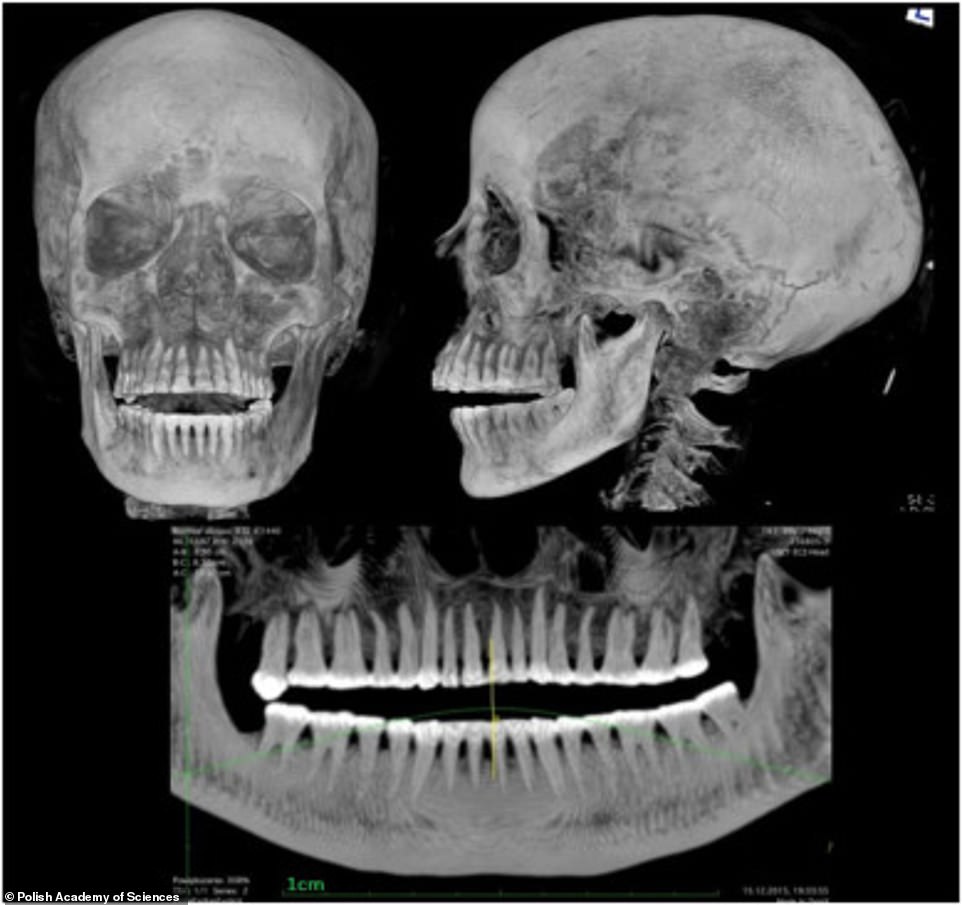

▼近年來波蘭科學院啟動一個研究項目,研究人員用X光和電腦斷層掃描博物館內所有的木乃伊,這才發現這具木乃伊並不是男性,而是女性。

▼研究人員進一步發現,這具木乃伊生前有孕在身。她是20到30歲之間過世的,腹中的胎兒大約26到30週大。木乃伊的身上還配有護身符,生前可能是貴族階級。